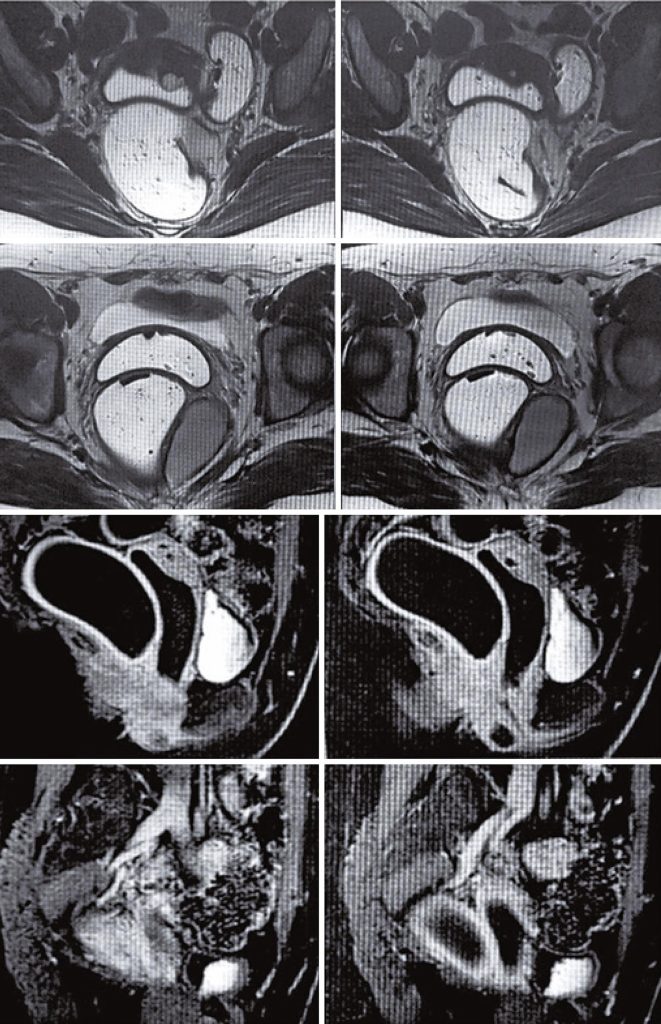

Tailgut cysts are rare congenital lesions that are remnants of the embryonic hindgut. This abnormality presents with non-specific symptoms or no symptoms; therefore, misdiagnosis is common. Here, we present four cases of tailgut cysts that were successfully removed using a robotic surgical approach. A 42-year-old woman with tenesmus, pain in the right gluteal region, and discomfort in the rectal region during evacuation was referred to our medical center. Another patient was a 28-year-old woman who presented with the same symptoms to our general practitioner. Both patients underwent upper abdominal and pelvic magnetic resonance imaging that revealed a tailgut cyst. Further, a 36-year-old woman was referred with coccyx and hypogastric pain. Magnetic resonance imaging revealed two pararectal cystic formations. She underwent robot-assisted surgery, and after analysis by a pathologist, the conclusion was that the tailgut cyst was associated with scarring fibrosis. A 55-year-old woman with posterior epigastric pelvic pain associated with heartburn underwent robot-assisted surgery to resect a retroperitoneal tumor. These cases highlighted the importance of tailgut cysts in the differential diagnosis of rectal lesions. Surgical treatment is preferred because malignant transformations can occur. The difference between laparoscopic and robotic approaches is the better visualization and stability of the latter, inducing less tissue damage. Robotic resection is a safe procedure, especially in patients with a narrow pelvis, because it reduces tissue damage.